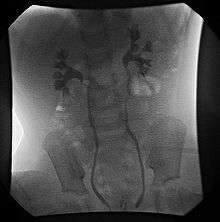

- Cystography

- Fluoroscopic voiding cystourethrogram (VCUG)

VCUG is the method of choice for grading and initial workup, while RNC is preferred for subsequent evaluations as there is less exposure to radiation. A high index of suspicion should be attached to any case where a child presents with a urinary tract infection, and anatomical causes should be excluded. A VCUG and abdominal ultrasound should be performed in these cases